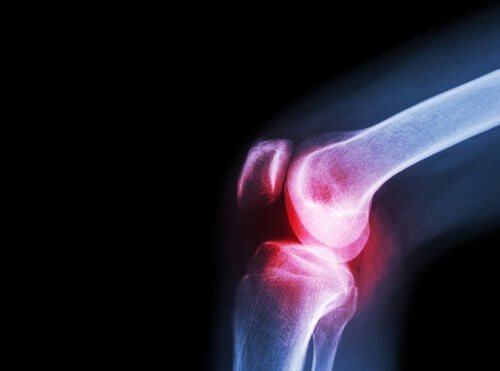

Questo farmaco viene prescritto nei casi in cui è richiesto un trattamento dei processi antinfiammatori e di dolori quali quello lombare, ai denti e alle articolazioni.

Allo stesso tempo, è indicato per il trattamento cronico del dolore e dell’infiammazione associati a processi cronici delle articolazioni: artrosi, artrite reumatoide e spondilite.

L’aceclofenac è indicato anche in caso di artrosi. Si tratta di un’altra patologia reumatica che danneggia la cartilagine delle articolazioni.

All’interno delle articolazioni c’è un fluido conosciuto come liquido sinoviale, prodotto dalla membrana sinoviale. Le estremità delle ossa che si uniscono per formare l’articolazione sono ricoperte dalla cartilagine articolare. Quando questa cartilagine si vede danneggiata, si scatenano dolore, rigidità e incapacità funzionale.

È importante distinguere questa malattia dall’artrite. Quest’ultima si sviluppa a causa di un’infiammazione dell’articolazione, non per l’usura della cartilagine. Tuttavia, entrambe causano dolore, per cui l’aceclofenac è efficace per trattare i sintomi di entrambe.